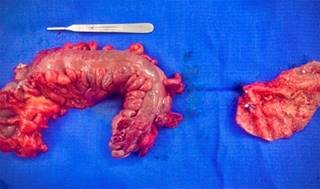

Se identificó colección en región inguinal izquierda con porción de colon sigmoides adherido firmemente, posterior a su liberación se encontró malla protésica adherida a la pared del colon sigmoides con migración intraintestinal (Figura 1). Se realizó procedimiento de Hartman con retiro de material protésico (Figura 2).

Figura 2: Pieza quirúrgica de colon sigmoides y malla protésica tipo 3Dmax.